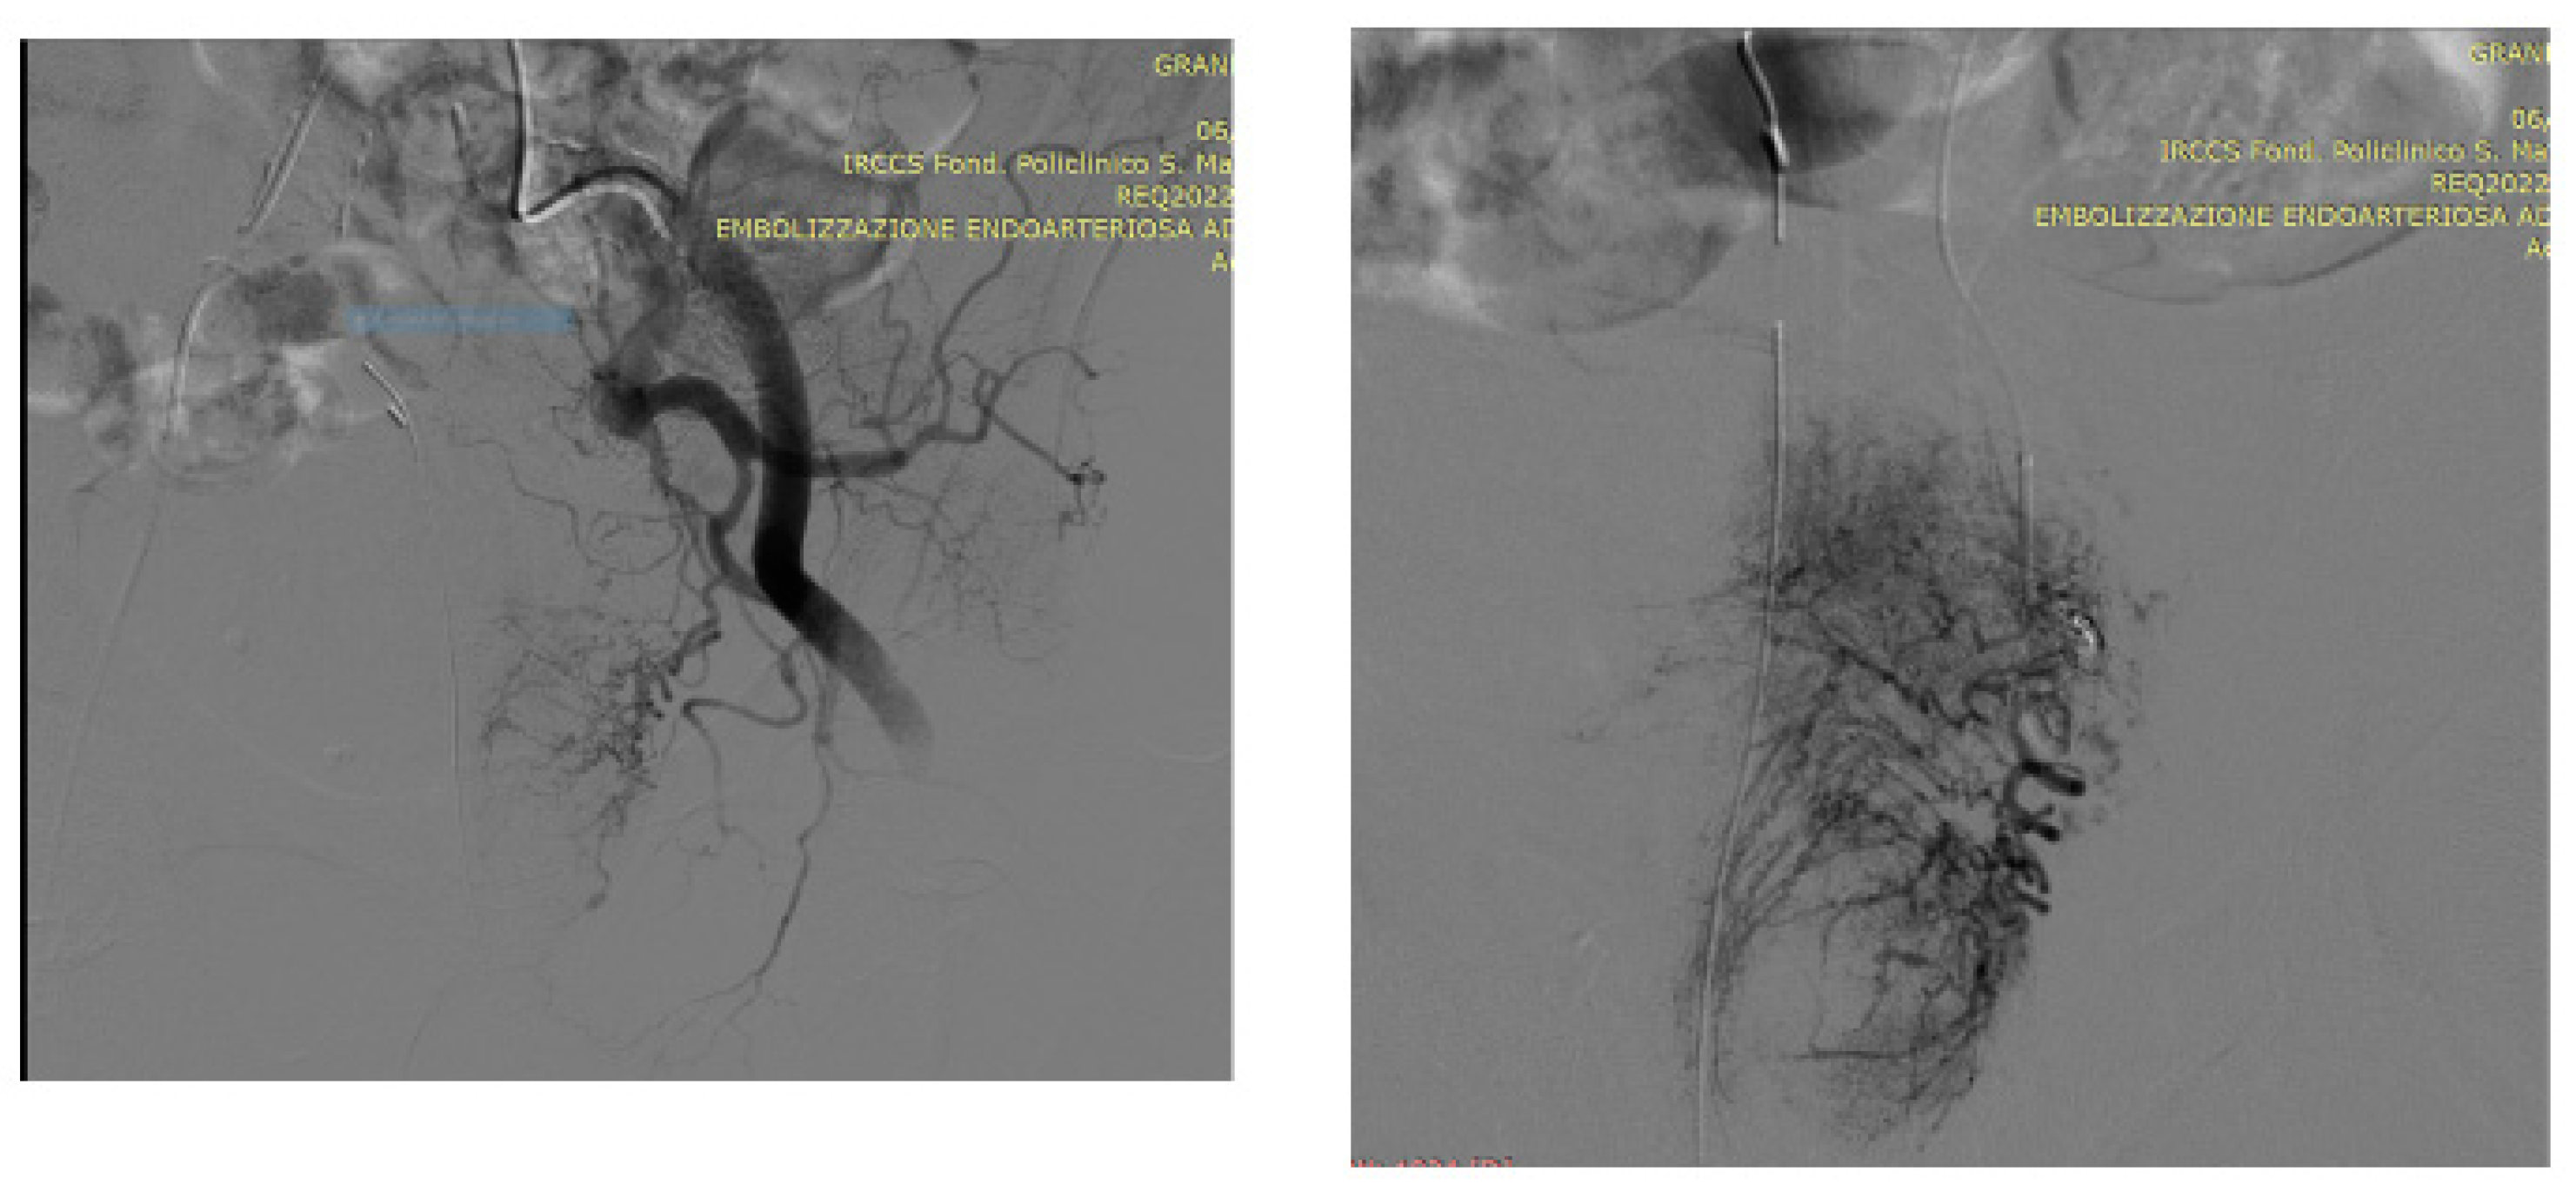

5.1. Technical details of PAE